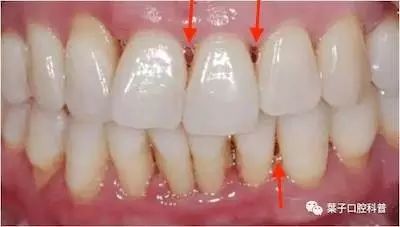

如果两颗牙齿之间的牙龈乳头退缩(牙龈萎缩),就会造成两颗牙齿之间下方出现空隙,食物就比较容易在嘴唇、脸颊和舌头的运动作用下,水平地进入了间隙,造成了塞牙的现象。